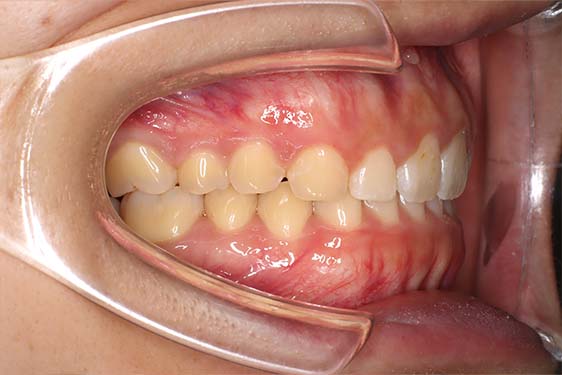

主訴かみ合わせが深く下の前歯が見えないのが気になる

治療計画かみ合わせが深く下の前歯が見えないとのことで来院。抜歯を行わず遠心移動を中心に拡大とディスキングを併用しインビザラインで治療を行いました。

左上に乳歯が残っていましたが歯根も長く、長期に保存することが可能と考え、ご本人と相談の上で抜歯は行わず、前歯部圧下を行い過蓋咬合の改善を図りました。アライナーの装着時間を可能な限り長く、かつアライナーチューイも適切に使用していただけたため良好な結果が得られました。